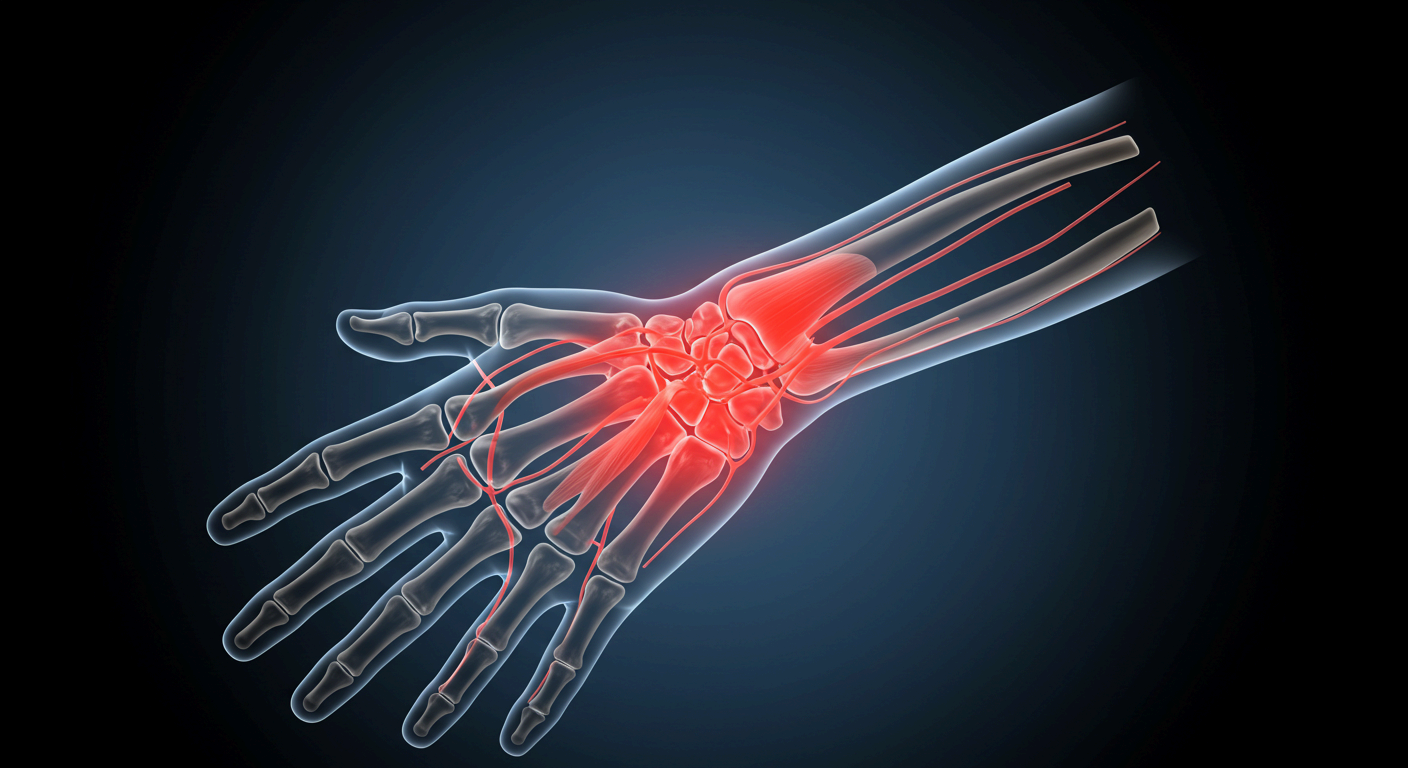

손목은 우리 손과 팔을 연결하는 중요한 관절로, 하루에도 수백 번씩 움직이게 됩니다. 키보드를 두드리거나 스마트폰을 스크롤하고, 물건을 들거나 청소를 하는 모든 행동에 손목이 관여하죠. 그런데 이런 반복적인 사용이 누적되면 손목에 미세한 손상이 반복적으로 축적되며 통증으로 이어질 수 있습니다.

손목에는 정중신경이라는 신경이 지나가는데, 이 신경이 반복적인 압박을 받으면 손가락 저림, 통증, 근력 약화 등의 증상이 나타납니다. 키보드, 마우스, 스마트폰 등을 자주 사용하는 사무직 근무자나 디지털 기기를 오래 사용하는 분들에게 흔히 나타나죠.

나이가 들면서 손목 관절의 연골이 닳고 뼈끼리 부딪히면서 퇴행성 관절염이 생길 수 있습니다. 또한 류마티스 관절염처럼 면역 시스템이 손목 관절을 공격하는 질환도 통증의 원인이 될 수 있습니다.